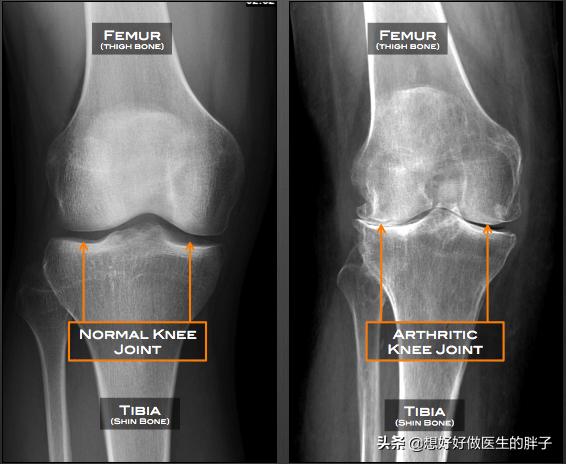

●膝関節のX線検査膝のレントゲンは、患者が著しい骨粗鬆症であるかどうか、関節腔に著しい狭窄があるかどうかを判断することができる。骨関節炎が存在するのだろうか?関節リウマチ。あるいは、他の一般的な膝の問題もある。

下の写真でわかるように、関節が発達しているのが典型的だ。目に見える隙間、狭い骨形成、より重い関節の骨粗鬆症。このような患者に明らかな異常感覚や痛みがある場合、硝酸ナトリウムの関節内注射や絶え間ない鎮痛剤の内服によって、患者は大きな痛みに苦しむことになるが、これは問題の解決にはあまり役立たない。